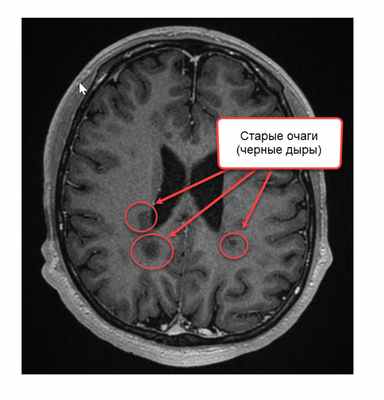

Кроме активных, копящих контраст очагов на T1-взвешенном изображении видны старые многолетние очаги, внутри которых идет или произошел процесс разрушения аксонов (отростков нейронов). Их обозначают термином «черная дыра» (black holes). При нахождении таких очагов мы говорим, что рассеянному склерозу уже несколько лет.

- появлением новых очагов и увеличением старых;